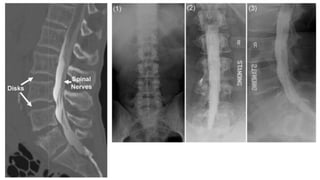

Mielografia

• Prueba radiológica que permite ver la médula espinal y sus raíces

nerviosas

• Utilizada para visualizar el espacio subaracnoideo espinal mediante la

introducción de un contraste iodado

• Consiste en realizar una punción lumbar y tras extraer varios mililitros de líquido

céfalo-raquídeo se administra un contraste radiopaco

• Posteriormente se realizan radiografías simples y se observa como el contraste

rodea la médula de tal forma que podremos ver indirectamente si existe algún

proceso que la afecte o detenga la difusión normal del contraste

• Puede completarse con una tomografía computada de columna que brinda mas

información puesto que permite hacer cortes axiales

Las principales indicaciones de la mielografía son aspectos como

sospecha de compresión espondilótica cervical, procesos expansivos a

nivel de cualquier punto de la médula o paraplejias agudas por

compresión medular